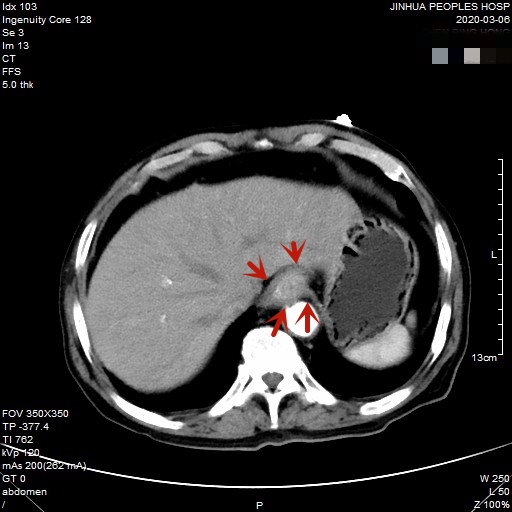

医生予以进一步检查CT增强发现肿瘤倒是没有明显侵犯周围脏器或结构,请我去会诊后,仔细阅片,发现从影像上看还是能够根治性切除的。所以转来胸外科拟进一步行手术治疗。下面是其CT增强的图像:

以上图片红色箭头所指处为贲门部肿瘤